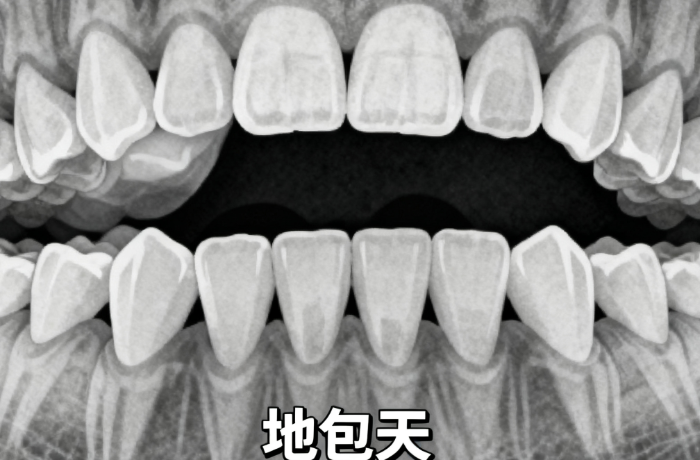

很多人誤以為“只要粘上托槽就能排齊牙齒”,實(shí)則正畸是高度依賴醫(yī)生經(jīng)驗(yàn)的個(gè)性化醫(yī)療行為。港城口腔的正畸由行家主治醫(yī)師領(lǐng)銜,團(tuán)隊(duì)特點(diǎn)包括:

• 擅長(zhǎng)青少年早期干預(yù)、成人復(fù)雜錯(cuò)頜畸形、正畸-修復(fù)聯(lián)合治療

• 堅(jiān)持“面型協(xié)調(diào)優(yōu)先于單純排齊”的美學(xué)理念,避免“牙齊了但嘴突了”

• 所有方案經(jīng)頭影測(cè)量+模型分析+面部分析三重評(píng)估后制定